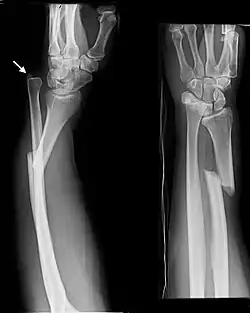

Uma fratura de Galeazzi é uma fratura da região distal do rádio com ruptura da membrana interóssea e da ligação com a ulna, com subluxação da ulna.